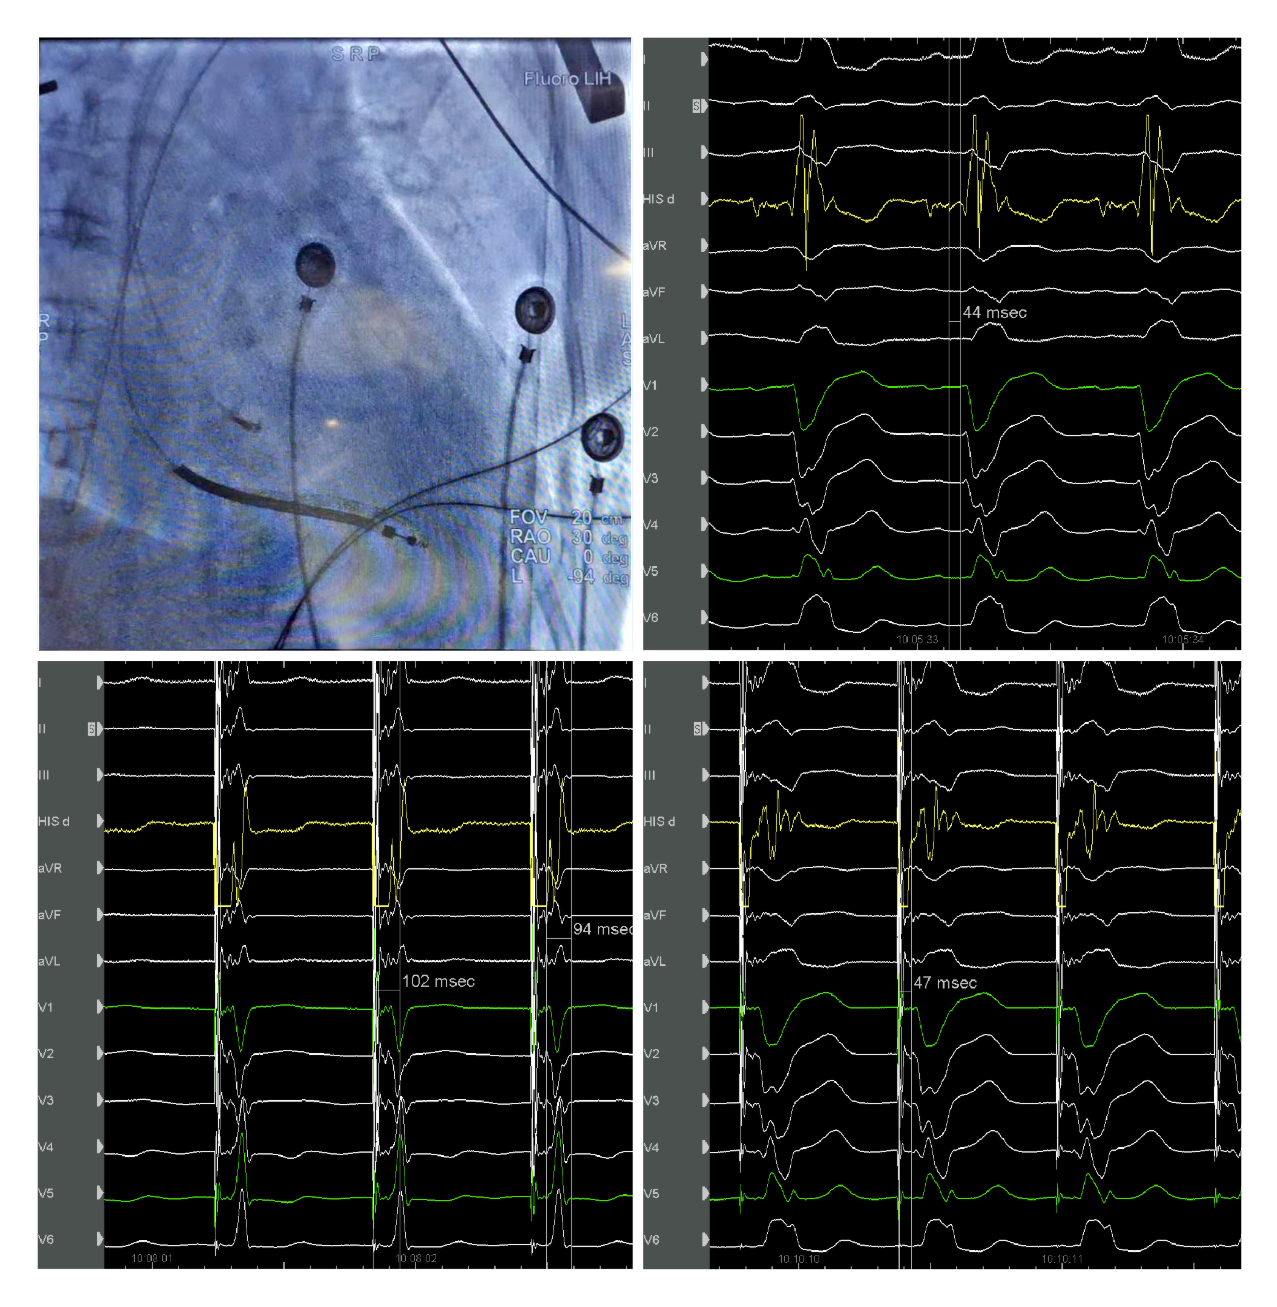

国产自拍 起搏团队演示了一例左束支起搏纠正完全性左束支阻滞用于治疗经典CRT适应症的病例。该患者为女性, 69岁,诊断:扩张型心肌病,完全性左束支传导阻滞,心功能III级,心电图显示经典完全性左束支阻滞图形,QRS193ms,心超LVD 73mm,EF 30%,符合CRTD适应症。术中顺利穿刺左侧腋静脉,在C315鞘管导引下3830电极标记到HIS电位,高电压起搏可纠正左束支阻滞,但纠正阈值较高8V/1.5ms。

(上图左上为希氏束的影像位置;右上为希氏束电位图;右下为低电压选择性希氏束起搏波型与自身一致;左下为高电压8V/1.5ms希氏束起搏纠正完左)

随后3830导线往心尖方向前移1cm拧入,同时监测起搏图形及单极阻抗,到位后起搏心电图显示不完全性右束支阻滞图形,左束支阻滞消失,测量V5导联左室达峰时间84ms,单双极高低电压起搏一致,提示夺获了左束支,夺获阈值0.7V/0.5ms。

(上图中左上为单极高电压起搏,右上为单极低电压起搏,左下为双极高电压起搏,右下为双极低电压起搏)

之后顺利植入心房导线及除颤导线,连接CRTD,调整AV间期融合右束支下传后得到完全正常化的QRS图形,起搏QRS时限97ms。